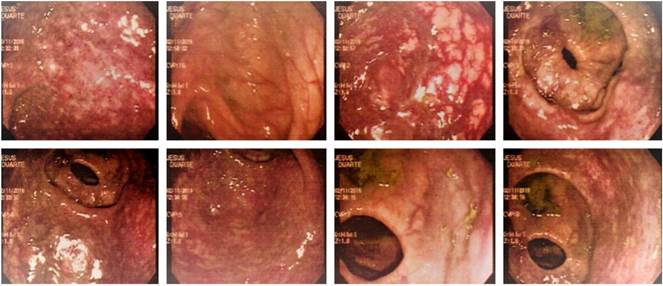

Se trata de un paciente masculino, de 18 años de edad, llevado al servicio de urgencias por cuadro clínico de más o menos 1 mes de evolución consistente en sangrado rectal en abundante cantidad con la defecación, acompañado de astenia, adinamia y palidez generalizada, sin dolor abdominal, ni fiebre, ni otros síntomas asociados. Al examen físico se encontró el paciente con palidez mucocutánea marcada y signos vitales estables; se realizó un colon por enema, el cual se reportó normal; y también se realizaron paraclínicos de extensión en los que se encontró un síndrome anémico con hemoglobina de 5,8 y hematocrito 18, que conlleva al estudio de su causa. Posteriormente, se realizó una colonoscopia que mostró a nivel de recto y sigmoides una lesión extensa que compromete toda la circunferencia, de coloración violácea con redundancia de trama vascular compatible con hemangioma colónico (Figura 1). El paciente fue llevado a cirugía y, finalmente, mediante el estudio de patología se confirmó el diagnóstico de hemangioma cavernoso del colon sigmoide.